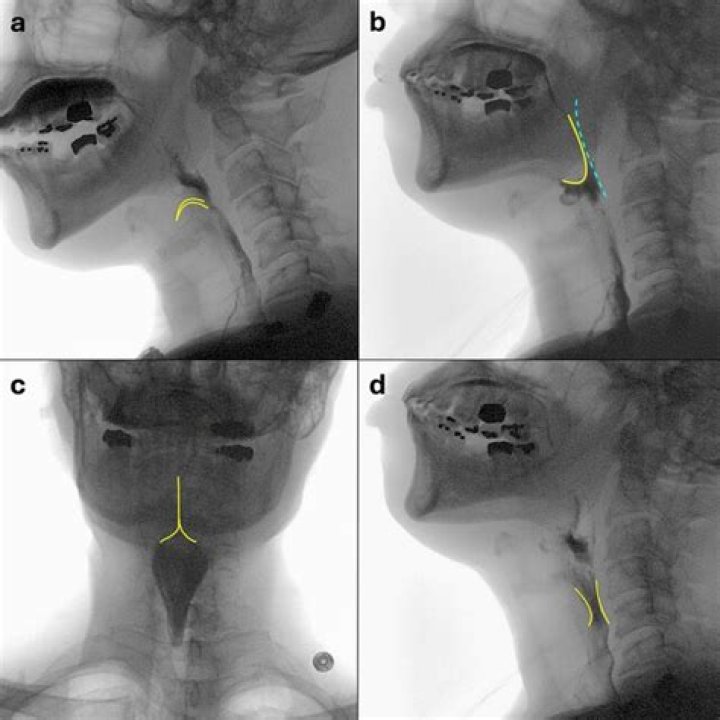

How do you perform a barium swallow?

Laryngeal Vestibular Penetration Laryngeal vestibular penetration occurs when barium enters the laryngeal vestibule but does not pass below the level of glottis through the true vocal folds [40].

Aspiration is defined as passage of materials through the vocal folds, and laryngeal penetration is defined as passage of materials into the larynx, but not through the vocal folds.

Abstract. The development and use of an 8-point, equal-appearing interval scale to describe penetration and aspiration events are described. Scores are determined primarily by the depth to which material passes in the airway and by whether or not material entering the airway is expelled.